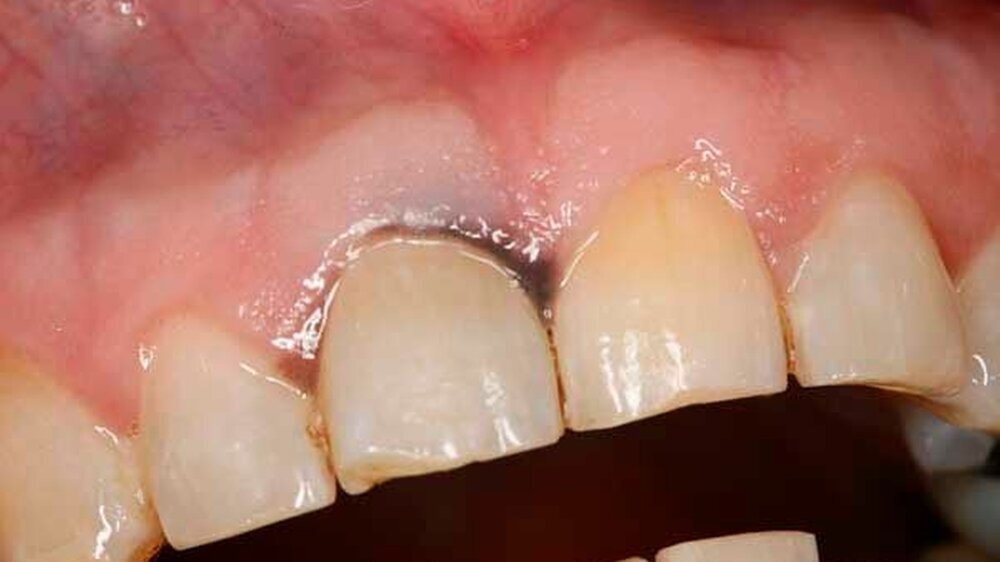

Bei der Aufnahmeuntersuchung zeigte sich eine schwärzliche, circa 2 cm x 1,5 cm messende, unregelmäßige Makula der Mundschleimhaut mit unscharfer Begrenzung, die sich von der marginalen Gingiva in regio 11 in Richtung des harten Gaumens erstreckte (Abbildung 1). Die sonografische Untersuchung der Halsweichteile war unauffällig, die Panoramaschichtaufnahme zeigte einen konservierend und prothetisch suffizient versorgten, altersentsprechenden Normalbefund. Die Schleimhautveränderung war bereits klinisch hochgradig verdächtig auf ein Mundschleimhautmelanom.